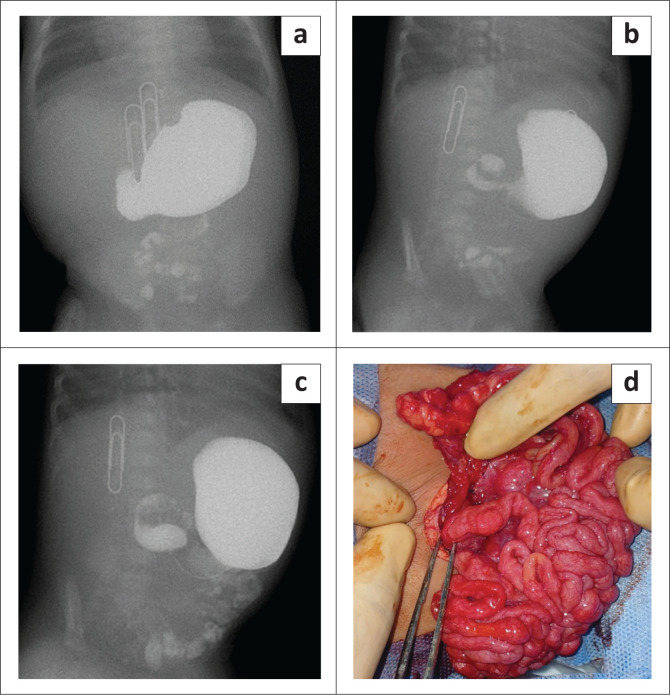

对于出现胆汁性呕吐的婴儿来说,紧急检查至关重要,因为这可能预示着肠梗阻。上消化道透视有助于诊断,但也并非没有挑战。本病例报告描述了一例罕见的新生儿肠旋转不良和中肠倒置,并伴有先天性腹膜包裹的并发症:本病例研究深入探讨了相关诊断难题,并强调了利用透视诊断复杂胃肠道疾病的价值。

Urgent investigation is crucial for infants with bilious vomiting, potentially indicating bowel obstruction. Upper gastrointestinal fluoroscopy aids diagnosis, but is not without its challenges. This case report describes a rare case of neonatal intestinal malrotation and mid-gut volvulus with an additional complication of congenital peritoneal encapsulation.

Contribution: This case study offers insights into associated diagnostic challenges and underscores the value of utilising fluoroscopy in diagnosing complex gastrointestinal conditions.